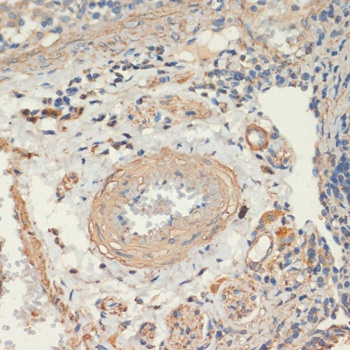

IHC: Formalin-fixed, paraffin-embedded human colon carcinoma stained with SMMHC antibody (MYH11/923).